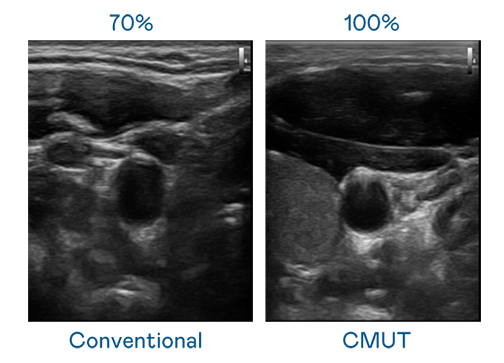

CMUT 技术是一种用电容式微机电元件来产生超音波讯号的技术。与传统 PZT 压电式技术相比,CMUT 频宽增加 30%,更宽频的超音波讯号让影像解析度大幅提升,是实现高影像品质医疗超音波扫描、促进精准医疗发展的关键技术。

超音波影像的解析度高低,首先取决于探头能发出的讯号频宽。九游会(J9) CMUT 可提供高清晰的超音波讯号,提供高频宽、高灵敏度、影像纹理细节更高的超音波影像,协助医护人员缩短影像判读时间及利用精准的医疗影像进行诊断。